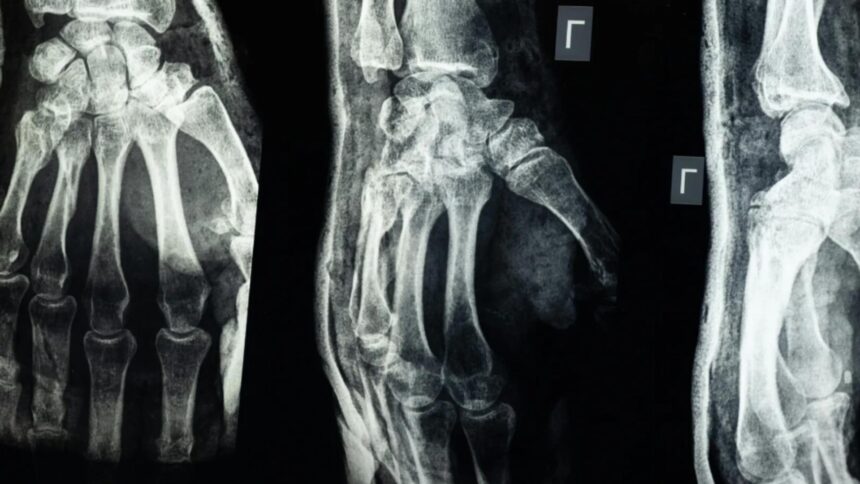

O echipă de cercetători din provincia Zhejiang, China, a dezvoltat un adeziv medical, denumit „Bone-02”, capabil să repare fracturile osoase în doar 2-3 minute. Acest produs ar putea înlocui implanturile metalice utilizate în prezent și ar putea reduce semnificativ timpul de recuperare al pacienților.

Testele de laborator și studiile clinice efectuate pe peste 150 de pacienți au demonstrat că „Bone-02” oferă o rezistență similară cu cea a implanturilor metalice. Forța de lipire depășește 400 de livre, iar rezistența la compresiune se ridică la aproximativ 10 MPa.